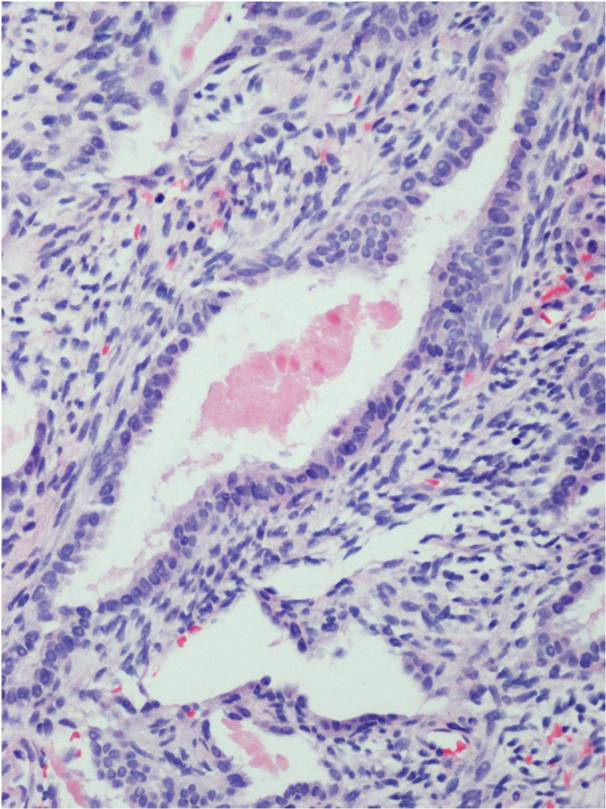

Microscopic Pathology

Synovial Sarcoma is composed of two different cell types

Spindle cell (small, uniform, and ovoid cells with pale nuclei and the cytoplasm is sparse)

Epitheloid cell (ovoid nuclei and abundant cytoplasm)

Biphasic form is composed of both epithelial-cell and spindle-cell components in equal proportions (Fig. 6-8)

Monophasic Fibrous type predominantly spindle cell.

Monophasic Epithelial type is difficult to differentiate from adenocarcinoma without cytogenetics and immunohistochemistry.

Poorly differentiated type demonstrates features of high grade small round cell tumor with dense cellularity, numerous mitotic figures, and areas of necrosis.

Inmunohistochemical profile: Vimentin (+), Cytokeratin (+), Epithelial Membrane Antigen EMA (+)